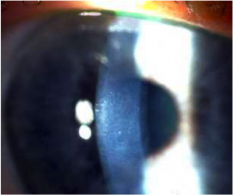

Η μεταμόσχευση ενδοθηλίου του Κερατοειδή DSAEK (Descemet’s Stripping Automated Endothelial keratoplasty) είναι μια τεχνική όπου τα ελαττωματικά ενδοθηλιακά κύτταρα αφαιρούνται από το μάτι και αντικαθιστώνται με μια νέα στοιβάδα ενδοθηλιακών κυττάρων.

Αυτή είναι μια πιο πρόσφατη μετεξέλιξη της κερατοπλαστικής που σε αντίθεση με τις μεταμοσχεύσεις ολικού πάχους περιλαμβάνει μόνο την αντικατάσταση της εσωτερικής στοιβάδας του κερατοειδούς που βρίσκεται το πρόβλημα και όχι όλο το κερατοειδή. Δεδομένου ότι με αυτή την πιο σύγχρονη τεχνική DSAEK δεν έχουμε τομές στο κερατοειδή και δε χρησιμοποιούνται ράμματα, σε αντίθεση με τη μεταμόσχευση κερατοειδούς πλήρους πάχους, το σχήμα του κερατοειδή παραμένει ανέπαφο επιτρέποντας πιο γρήγορη ανάκτηση της οπτικής.